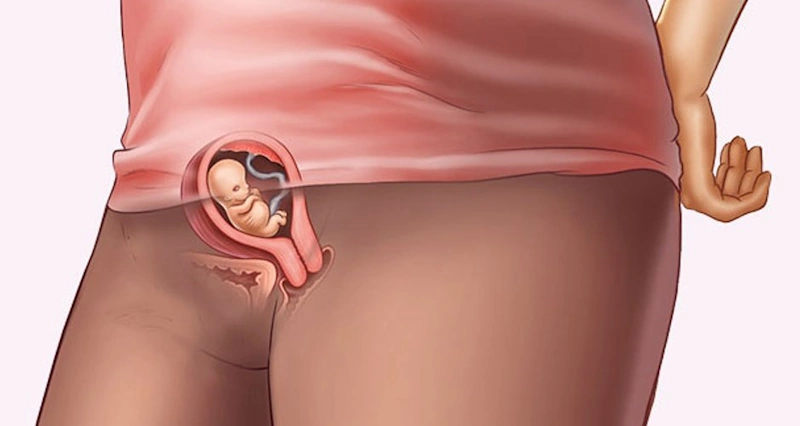

То ҳафтаи 7, шумо эҳтимолан ҳомиладор буданро эҳсос мекунед, ҳарчанд тағйироти беруна шояд намоён набошад. Мумкин аст бимӯдили либосатон маҳдуд шавад, хусусан агар ин ҳомилаи аввалатон набошад, зеро ҳомилапазирӣ ба таври назаррас васеъ мешавад.

Қисми болоии ҳомилапазирӣ, ки гардани бачадон ном дорад, мушакӣ ва чандир аст ва метавонад то 100 маротиба зиёдтар аз андозаи аслиаш дароз шавад, то кӯдакро нигоҳ дорад. Ҳоло бачадон таҳти устухони камар аст, вале дар чанд ҳафтаи оянда болотар баромада, байни меъда ва рӯдаҳо ҷойгир мешавад.